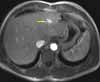

Abdominal MRI is performed to further delineate the hepatic masses. Based on the enhancement pattern during contrast administration, the lesions are characterized as hemangiomas. The largest lesion measures 16.51 mm (Figure 2).